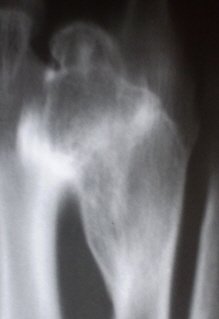

Иллюстрации 9, 10, 11, 12  демонстрируют структуру патологического образования – фрагменты томографических срезов.